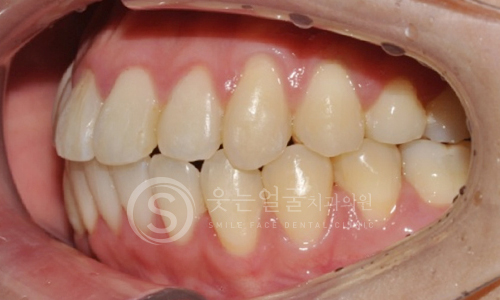

한눈에 보는

치아교정 전후사진